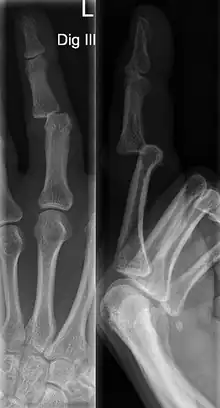

A jammed finger can generally be diagnosed via physical examination. The relative position of the bones of the finger give an indication as to potential dislocations or fractures.[3] However, it is recommended to seek medical attention regardless of whether or not a dislocation or fracture is evident.[6] This is because untreated jammed fingers can lead to future pain and stiffness, with joint surface fractures increasing the risk of arthritis.[6] The areas around the injury may be palpated in order to ascertain the areas of maximum pain.[2] If the injury is a joint injury (namely a sprain or dislocation), the point of maximum pain will be close to the joint rather than mid-phalanx (mid-bone).[2] Due to the risk of dislocations or fractures, stability testing is not recommended until after an x-ray has been conducted and the presence of a dislocation or fracture has been confirmed or rejected.[2] In extremely painful cases, a digital nerve block, where anaesthetic is injected in the web to either side of the affected finger, may be employed to enable assessment of the injury.[2] X-rays may be employed to achieve a more accurate diagnosis of a jammed finger, enabling the identification of varying types of dislocation or fractures. In order to account for all possibilities, it is recommended that a variety of views (lateral, oblique, and anteroposterior) are observed.[2]

Dislocations can be categorised based on location and type. The finger can be split into three bones and two joints in an alternating order. From the fingertip to the knuckle, these are as follows; distal phalanx, distal inter-phalangeal (DIP) joint, middle phalanx, proximal inter-phalangeal (PIP) joint, and proximal phalanx. DIP dislocations are much less common than PIP dislocations,[2] due to the "stability provided by strong collateral ligaments, palmar plates, and tendinous insertions, as well as the short lever arm of the distal phalanx".[7] Dislocations can be categorised based on the direction that the fingertip moves in relation to the knuckle, be it in the direction of the palm (volar dislocation), or the direction of the back of the hand (dorsal dislocation). Of the two, dorsal dislocations are more common.[3] If reduction has been attempted, an x-ray of the dislocation should appear concentric if successful.[2] However, if there is a fracture present, there will be a misalignment of the joint, which will be evident from the radiograph.[2] Bach suggests a referral to a hand surgeon if a misalignment is present.[2]

Fractures are instances where the bone's structural integrity has been compromised. This is indicated by midshaft pain, as well as visual midshaft angulation or rotation.[3] As with any skeletal injury, an x-ray can be conducted to verify the presence of a fracture.[1] The distal phalanx is especially vulnerable to avulsion fractures, where a fragment of bone is ripped off when the tendon separates from the phalanx.[1] Avulsion fractures are especially common following a first time dislocation.[1] These are especially concerning, as it may indicate a complete tear of the extensor digitorum tendon. If left untreated, this may lead to permanent DIP extensor lag (inability to fully straighten the finger).[8]